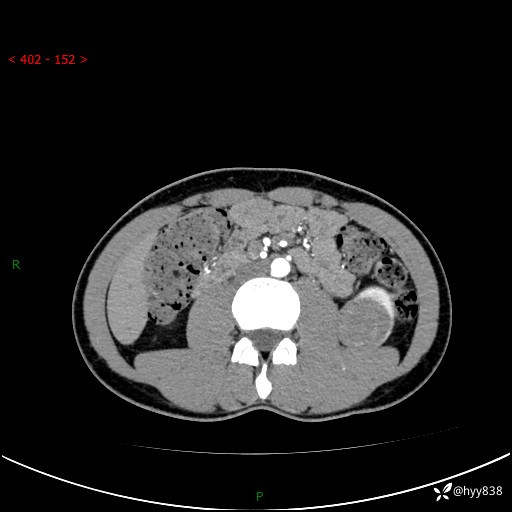

现病史:患者昨日中午进食后出现明显腹痛,腹泻,在我院急诊科行补液及对症治疗,双肾输尿管彩超提示左肾占位(5.2*4.3cm),平素无明显腰痛,无再发肉眼血尿等情况,现为求处理左肾占位,遂来我院,门诊以左肾占位收治入院。 患者起病以来,精神、食欲、睡眠尚可,大便可,小便如上,体力体重无明显下降。

双肾CT平扫+增强(三期)